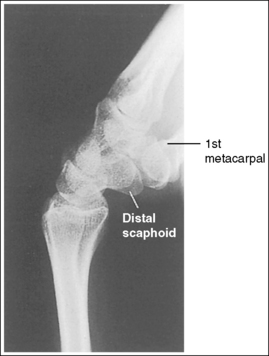

The wrist is in a lateral projection. The anterior aspect of the distal scaphoid and pisiform are aligned, and the radius and ulna are superimposed.

• A lateral projection of the wrist is accomplished by flexing the elbow 90 degrees and abducting the humerus until it is parallel with the IR, placing the entire arm on the same horizontal plane. Rotate the wrist into a lateral projection with its ulnar (medial) aspect against the IR (Figure 4-38). To ensure a true lateral projection, place the palmar aspect of your thumb and forefinger against the anterior and posterior aspects, respectively, of the patient's wrist joint, as shown in Figure 4-39. Adjust wrist rotation until your thumb and finger are aligned perpendicular to the IR.

• Detecting wrist rotation. The relationship between the pisiform and distal aspect of the scaphoid can best be used to discern whether a lateral wrist projection has been obtained. On a lateral projection, these two carpals should be superimposed, with their anterior aspects aligned. When the wrist is rotated, the anteroposterior relationship between the distal scaphoid and pisiform changes, and the pronator fat stripe is obscured. If the anterior aspect of the distal scaphoid is positioned posterior to the anterior aspect of the pisiform, the patient's wrist was externally rotated (see Image 45). If the anterior aspect of the distal scaphoid is positioned anterior to the anterior aspect of the pisiform, the patient's wrist was internally rotated (see Images 46 and 47). A second method of determining how to reposition a rotated lateral wrist projection uses the radius and ulna. The ulna is positioned anterior to the radius when the wrist was externally rotated and the ulna is positioned posterior to the radius when the wrist was internally rotated. Because the exact amount of superimposition of the radius and ulna depends on the position of the humerus, and their poor positioning is not as sensitive, you should always view the pisiform and distal scaphoid relationship when determining whether the wrist is in a lateral projection.

The carpal bones do not indicate radial or ulnar deviation. The distal aspect of the distal scaphoid is aligned with the distal aspect of the pisiform.

• To obtain a neutral lateral wrist projection, align the long axes of the third metacarpal and the midforearm parallel with the IR. When the proximal forearm is higher or lower than the distal forearm, the wrist is radial-deviated or ulnar-deviated, respectively. In radial and ulnar deviation the distal scaphoid moves but the pisiform's position remains relatively unchanged. Radial deviation of the wrist forces the distal scaphoid to move anteriorly and proximally (Figure 4-40), causing the distal aspect of the distal scaphoid to be positioned proximal to the distal aspect of the pisiform (see Image 49). Ulnar deviation shifts the distal scaphoid posteriorly and distally (see Figure 4-40), causing the distal aspect of the distal scaphoid to be positioned distal to the distal aspect of the pisiform (see Image 50). The degree of pisiform and distal scaphoid separation is usually very small, because you would be unlikely to position a patient in maximum wrist deviation without being aware of the positioning error. To obtain optimal lateral wrist projections, however, you must learn to eliminate even small degrees of deviation.

The long axis of the first metacarpal is aligned parallel with the forearm.

• If the long axis of the first metacarpal is positioned adjacent to the second metacarpal and aligned parallel with the forearm, the patient's wrist is placed in a neutral position.